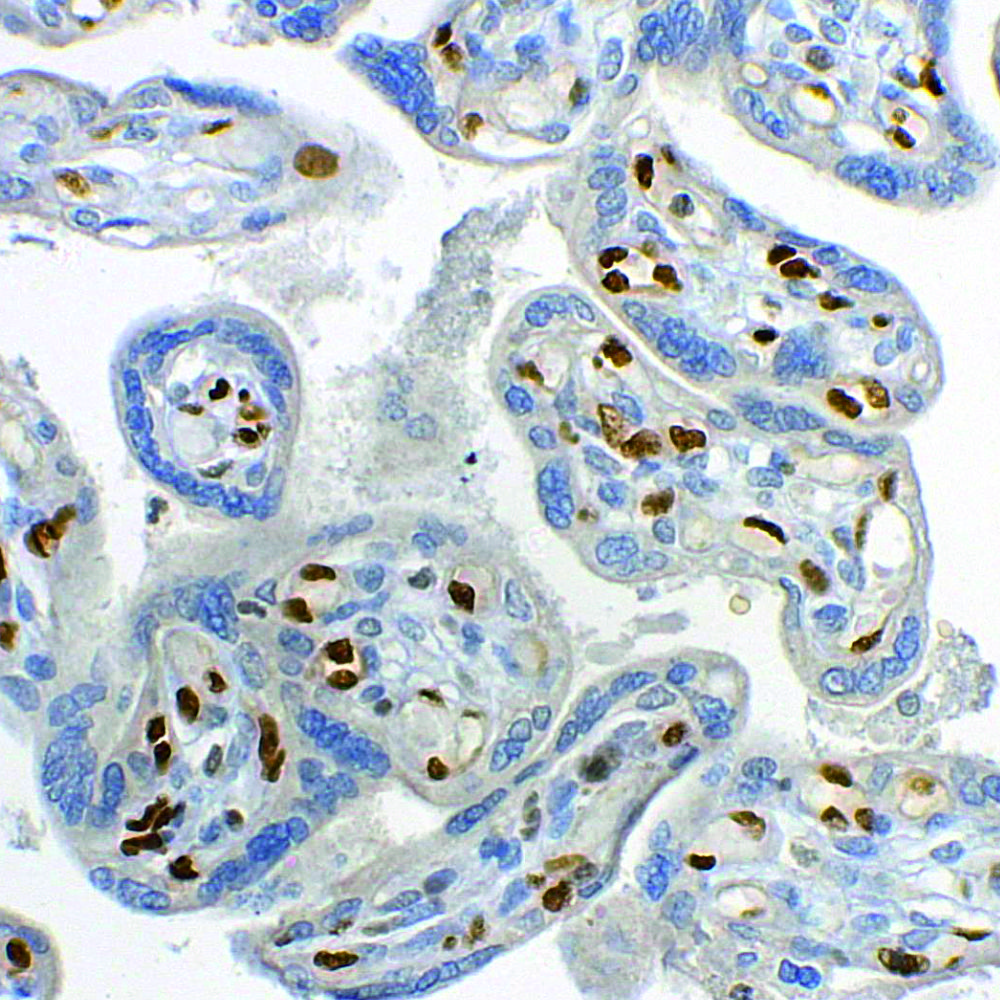

Revolutionizing Tissue Diagnostics with Precision

Complete IHC Solution

Detection System

Antibodies, Special pathology stains, HRP Detection system

Fully Automated

IHC system, Microtome, Flexigross, Antibody retrieval system etc.

Digital Solutions

Digital Scanner & Microscopy, Tissue Processor, slide dryer, etc.

Immuno-fluorescence

Tissue-Microarray, fluorescent components & Ancillaries

PathnSitu Biotechnologies

your IHC partner

Specializes in providing high-quality immunohistochemistry (IHC) solutions designed to enhance diagnostic accuracy and research outcomes.